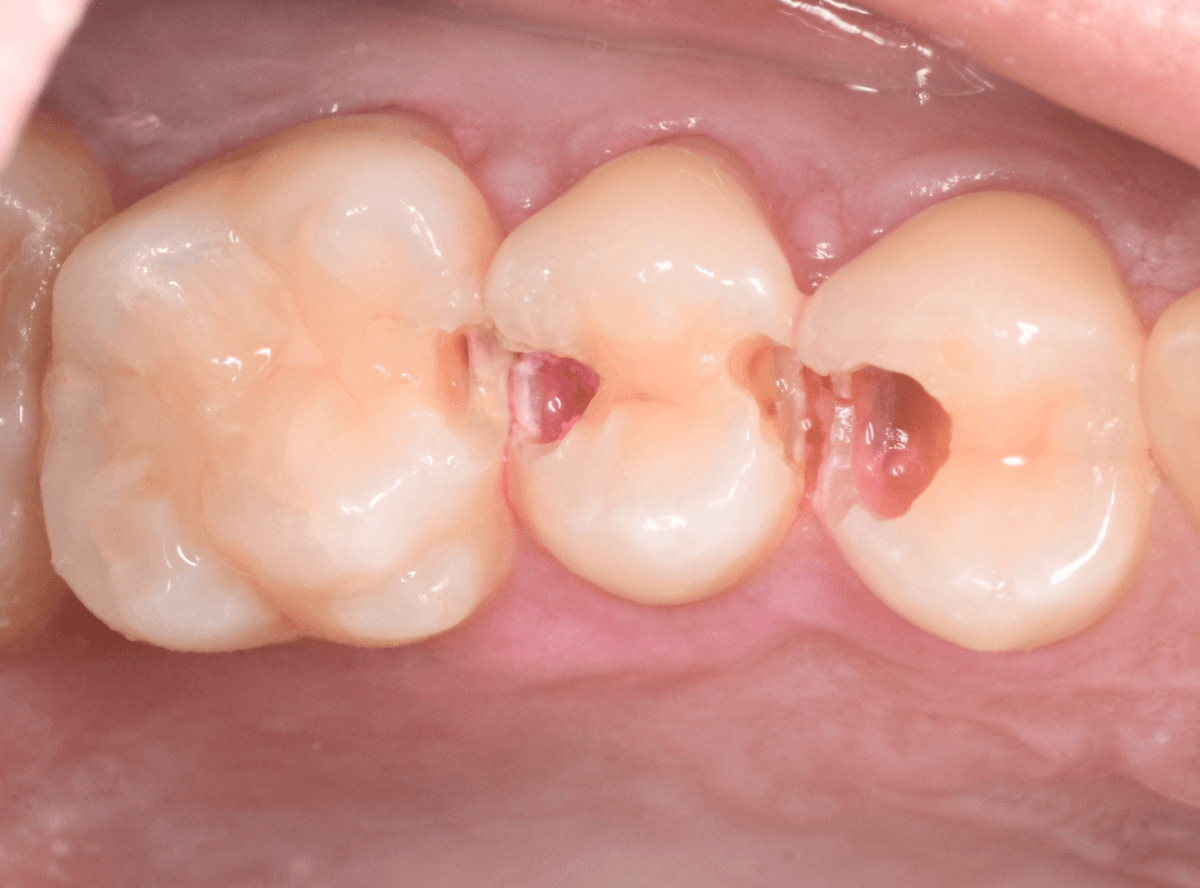

Case.22 痛みはないけど、歯のすきまから大きな虫歯

上の小臼歯の間が虫歯になっていた患者さんです。

症状はありませんし、見た目からも虫歯があるかはわかりませんでした。

治療を開始します。

ある程度、虫歯を除去したところで、う蝕検知液で確認します。

赤く染まっている部分が虫歯です。

まだまだ虫歯が中で残っている状況で、かなり深い虫歯なのが確認できます。

全ての虫歯を除去しました。

レントゲン写真からある程度確認出来ましたが、歯の神経スレスレまで虫歯が進行していました。

ここまで虫歯が進行していても、全く症状を感じない事も多いです。